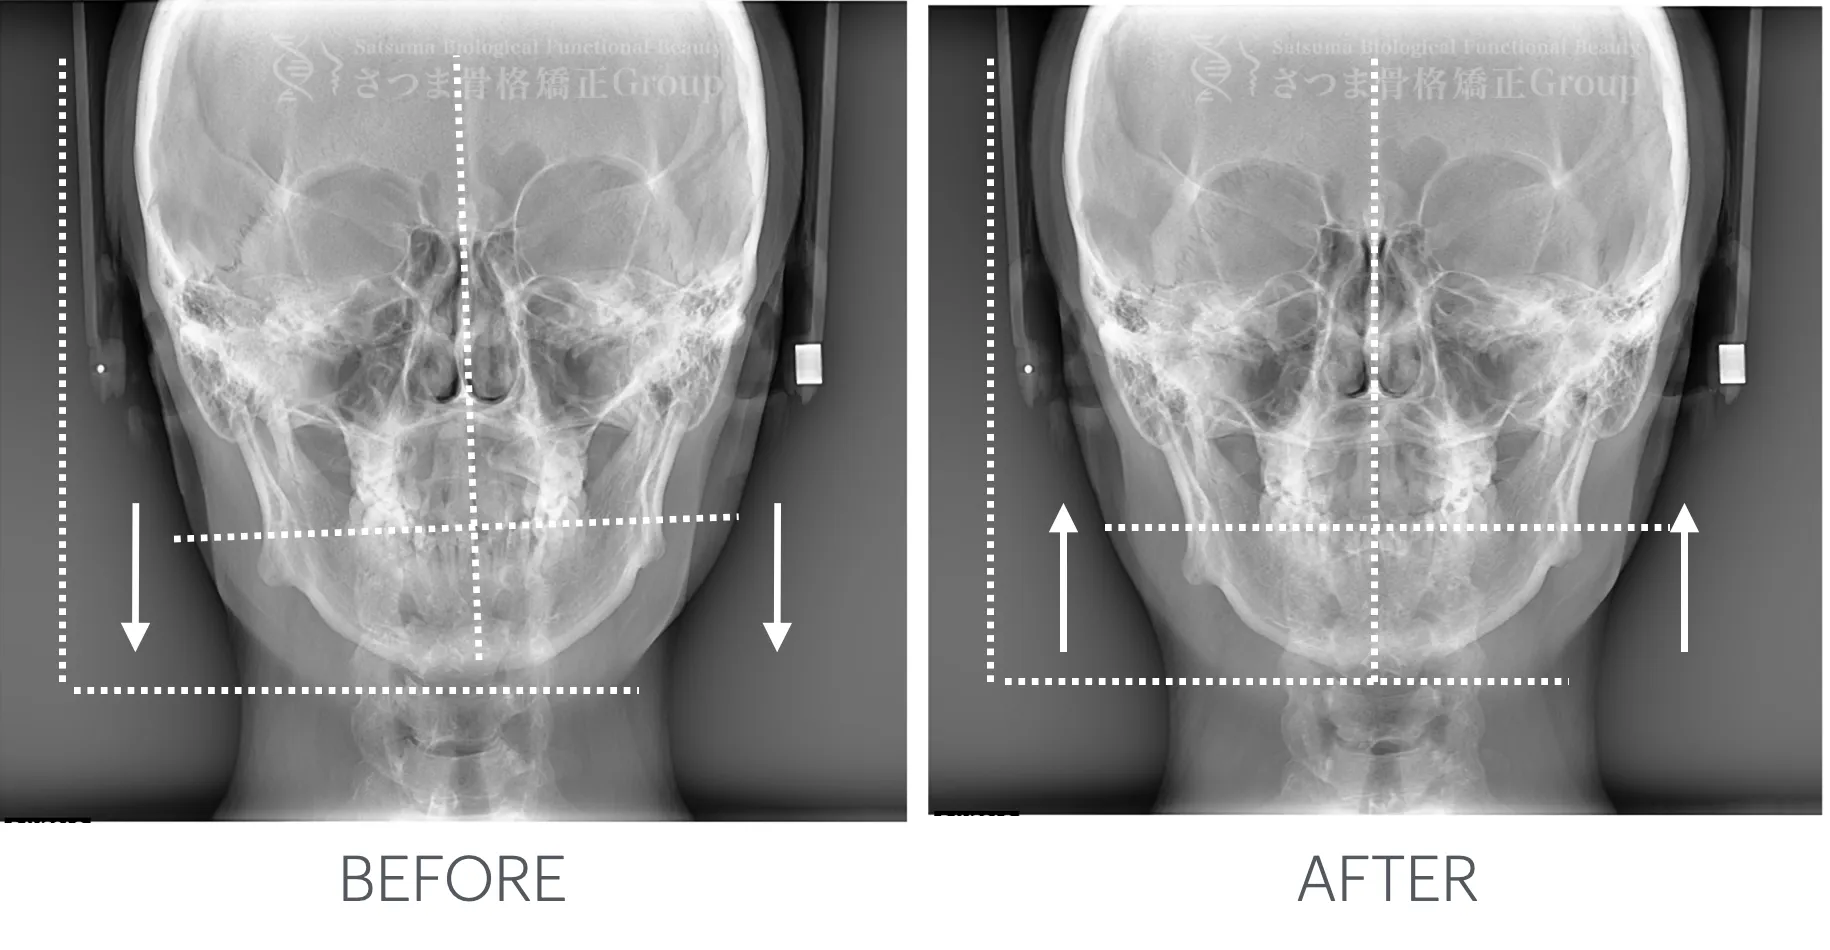

最新のCTスキャンによる顎・顔面・頚椎の立体画像検査を導入。

治療前後の変化を視覚的に確認できるため、

改善のプロセスを“見てわかる”形で効果を実感いただけます。